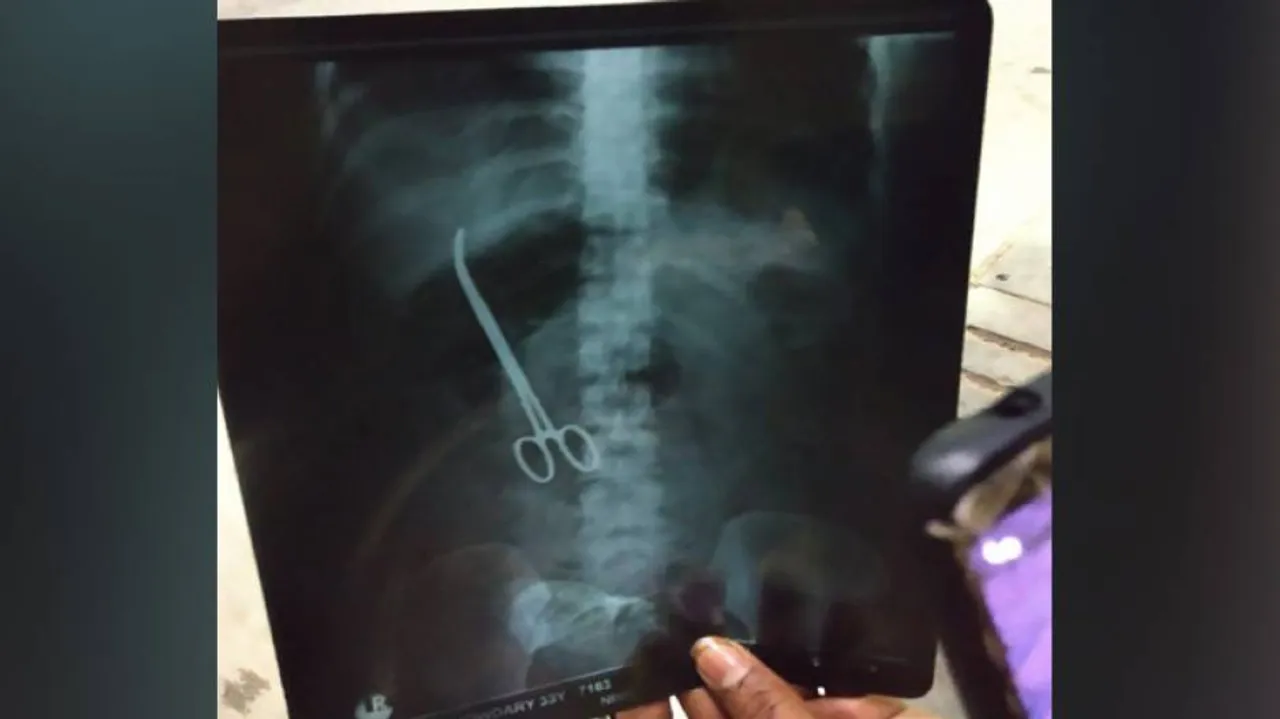

Hyderabad: In a shocking incident, doctors at Nizam's Institute of Medical Sciences (NIMS) here, left artery forceps in a patient's abdomen during a surgery.

This negligence by the doctors at the government-run super-speciality hospital came to light on Saturday when an X-ray revealed that a pair of forceps was embedded in the stomach of Maheshwari Chowdary.

The 33-year-old had undergone a surgery for hernia on November 2 last year. But even after the surgery she complained of severe abdominal pain and an X-ray report revealed that surgeons had accidentally left the surgery tool in her stomach.